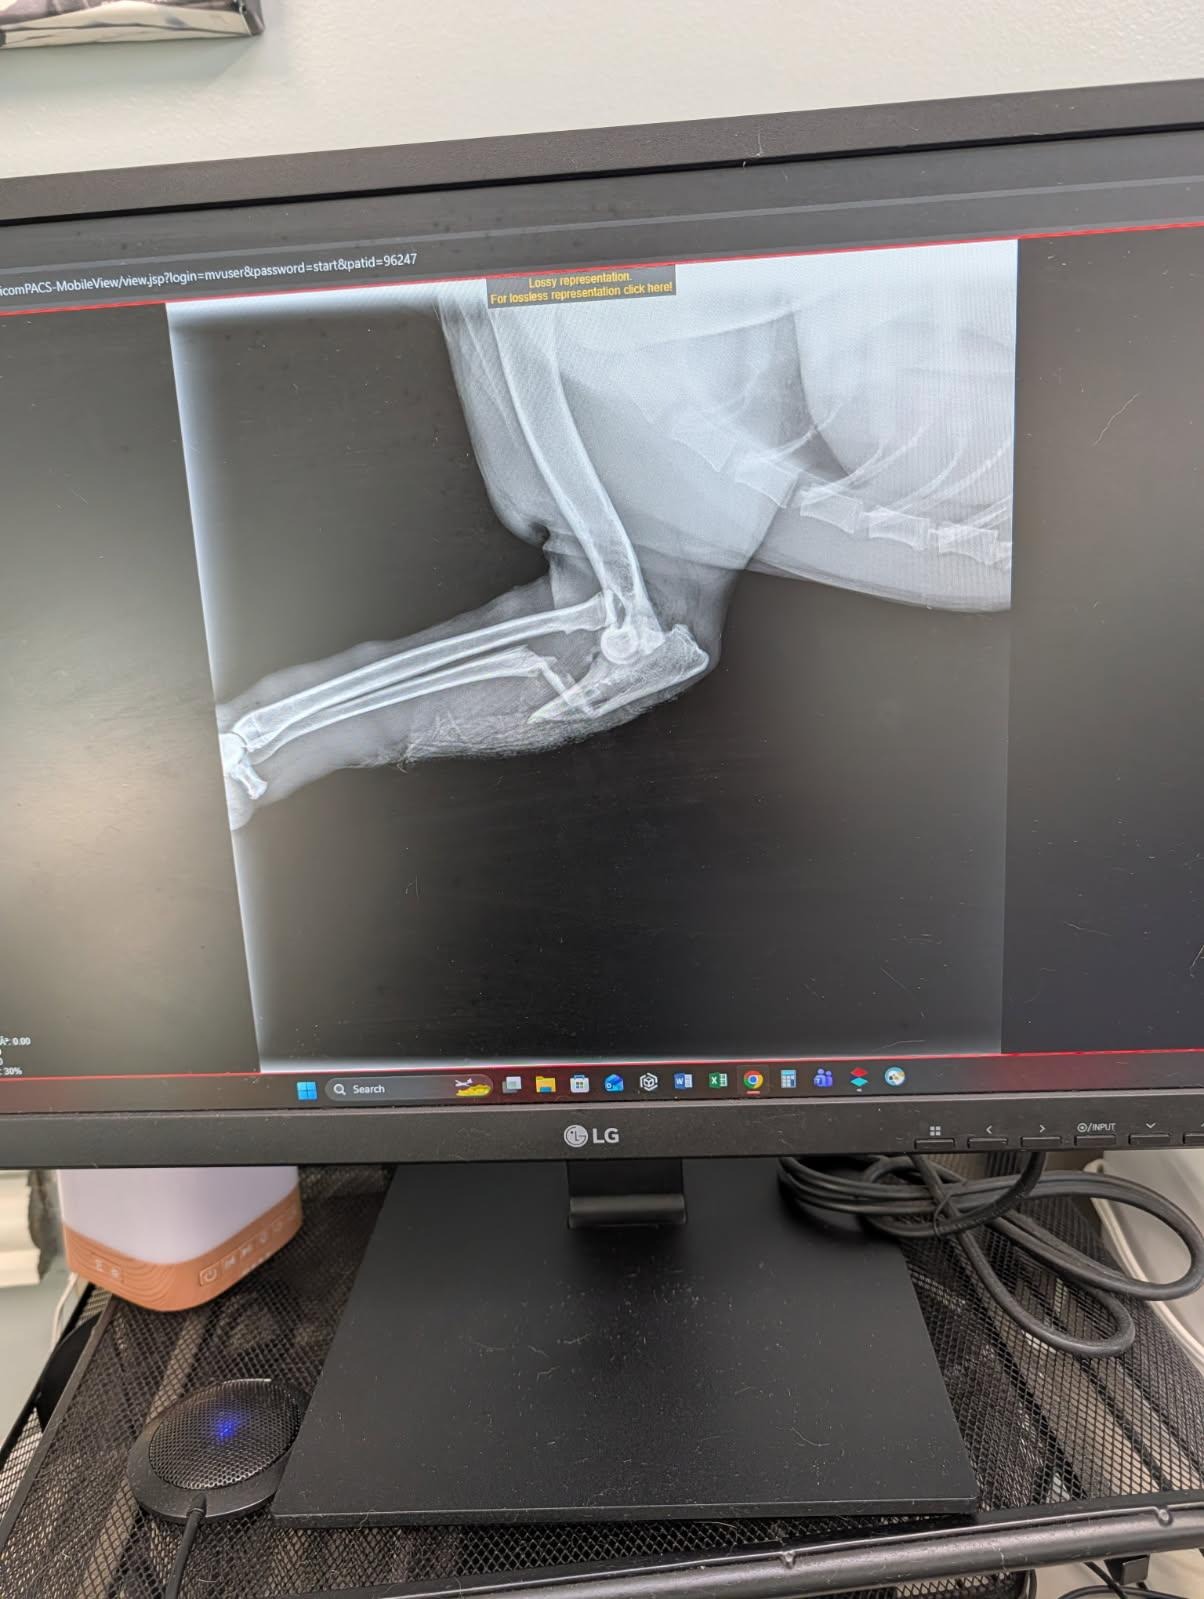

My dog Rosi means the world to me. Recently, she was hit by a car and suffered a broken front leg—one bone is broken and another is dislocated. It was a terrifying experience, and seeing her in pain has been heartbreaking. The vet told me that Rosi needs surgery to repair her leg, and the cost is more than I can handle on my own.

The surgery will help fix Rosi’s bones so she can walk and play again. On top of that, we have to drive an hour away to a specialist, and she’ll need medicine and special tools to help her recover. Every day, Rosi brings so much joy and comfort to my life. She’s not just a pet—she’s family, and I want to do everything I can to help her heal and get back to her happy, playful self.